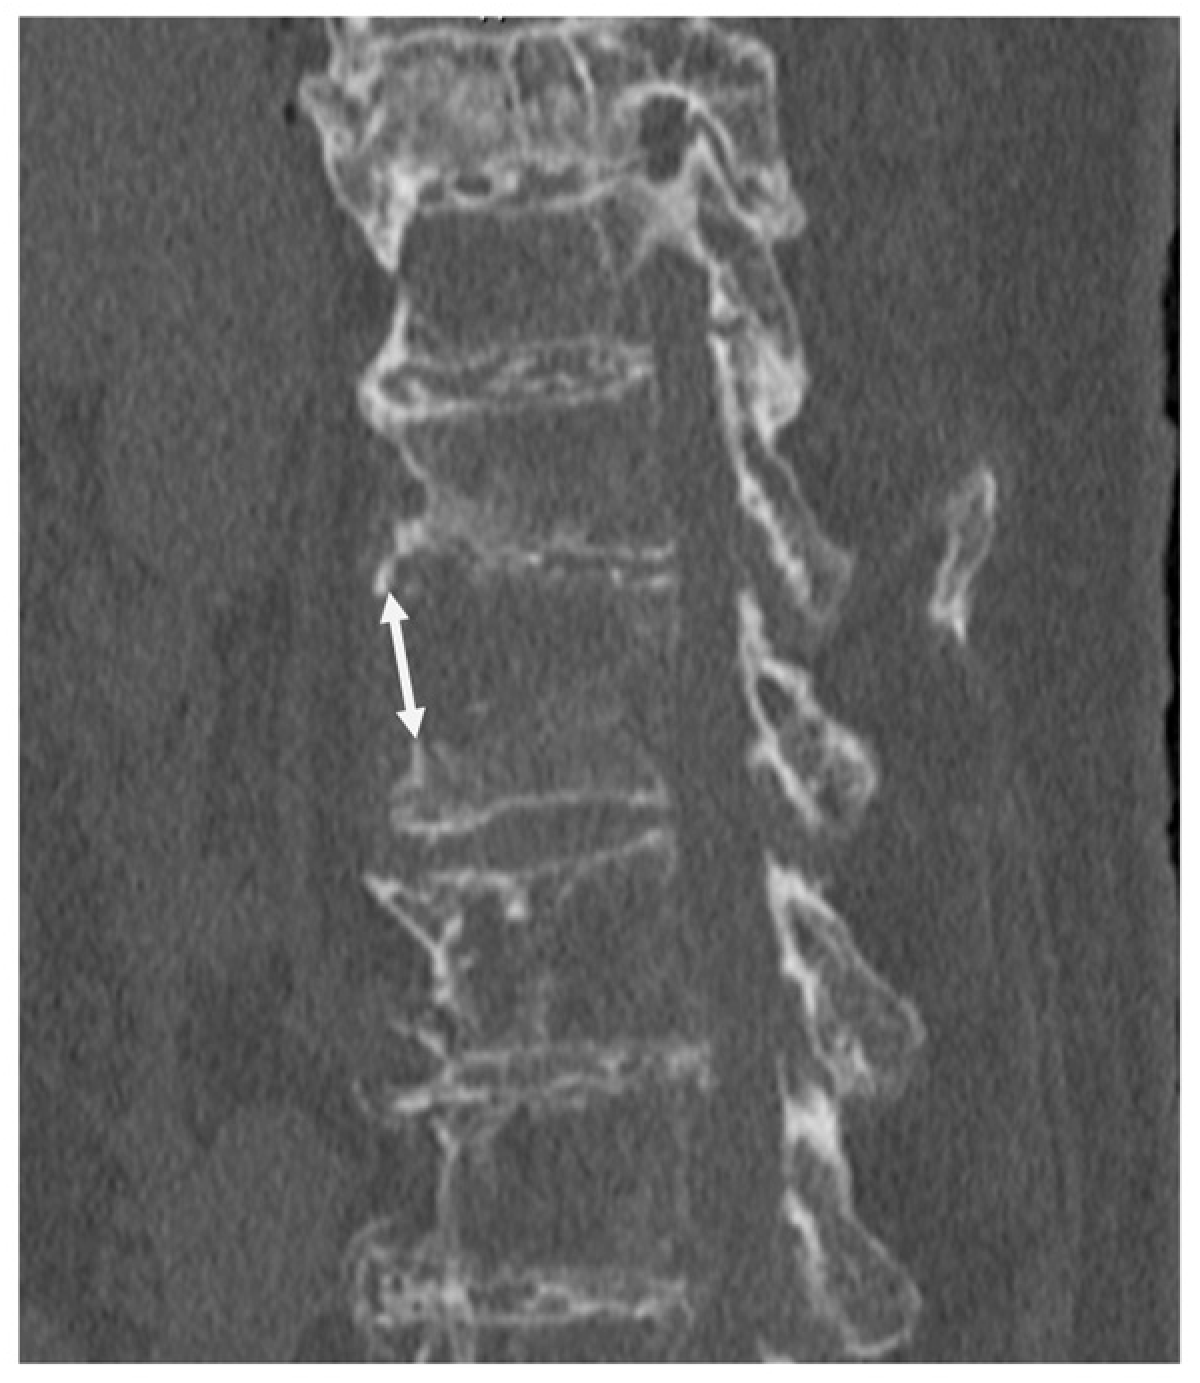

3.1. Case Presentation 1

3.2. Case Presentation 2